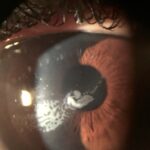

Imagen típica de un CE grado 3 que se extiende hacia el eje visual afectando a la visión del paciente.

La presentación típica del CE sintomático es la una “lengua” o “península” con aspecto geográfico o en huella dactilar, con nidos de células epiteliales de color blanquecino en su interior, que crece en la interfase desde los márgenes elevando el flap con tinción negativa en la superficie. En casos estacionarios es frecuente la presencia de una línea de demarcación que delimita el CE. También es frecuente observar cierto grado de haze en el flap, debido a queratolisis, en las zonas de CE. En casos severos el borde del flap puede aparecer engrosado y enrollado con aspecto grisáceo(5).